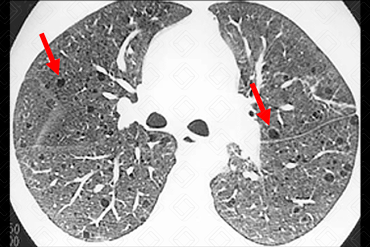

Texto alternativo para a imagem Créditos: Dra. Elazir Mota - Rio de Janeiro/RJ

Descrição da imagem: Tomografia computadorizada do tórax. Múltiplos cistos, dispersos pelo parênquima, em paciente do sexo feminino, compatível com linfangioliomiomatose.

• Tomografia computadorizada do tórax: Exame de escolha para avaliação de doenças pulmonares císticas. Observamos numerosos cistos com conteúdo aéreo, arredondados e dispersos difusamente pelo parênquima. Em alguns pacientes, há ruptura dos cistos mais subpleurais e surgimento de pneumotórax espontâneo.